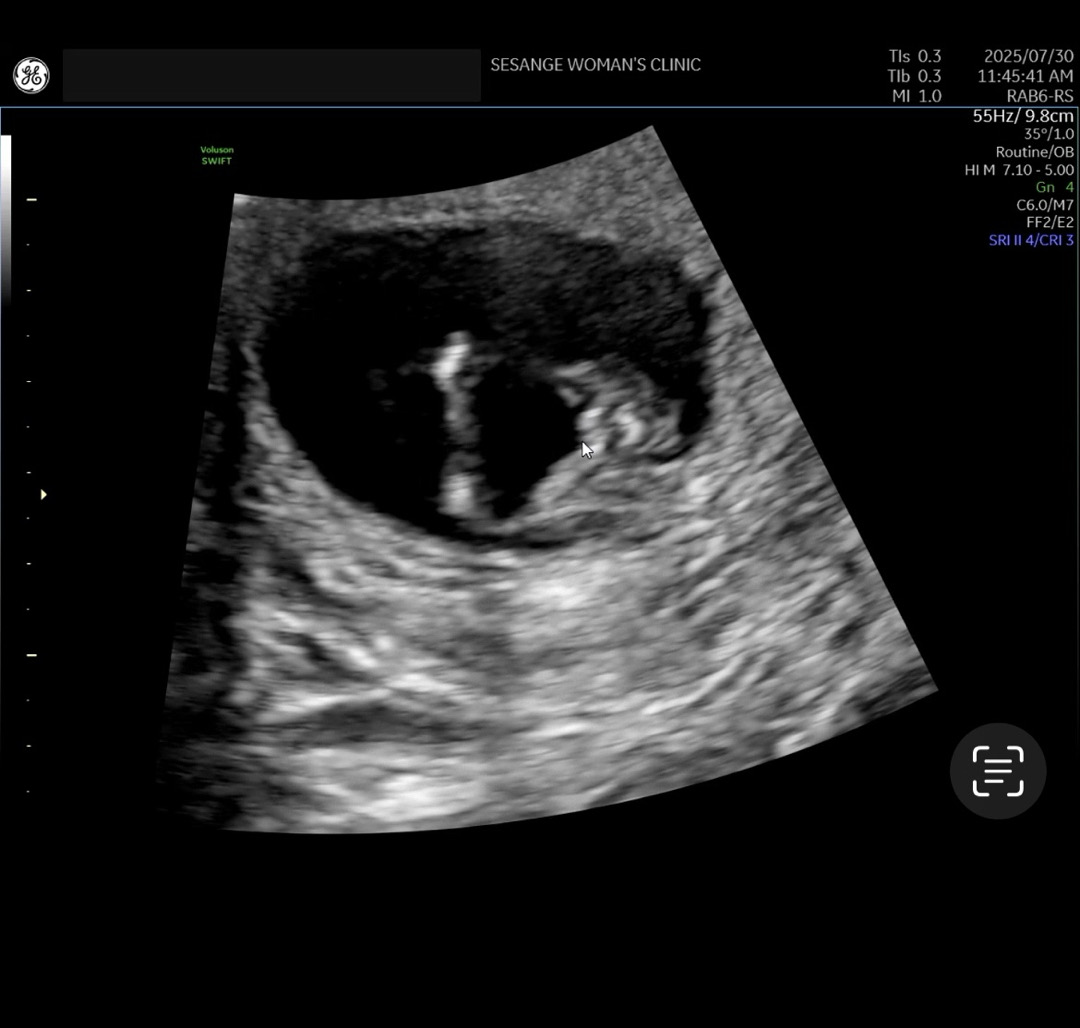

14주 초음파인데 딸일까옹???

처음 각도법으로는 아들같다고 소리를 많이 들었는데 14주 초음파 보니까 다리사이가 여자같다고 하는데 각도법 고수님들은 어때보이세용? 마우스 커서 부분이 생식기라고 하셨어요!

딸이에요!!!딸은 저렇게 마카롱(?)처럼 생겼더라구용 ㅎㅎ